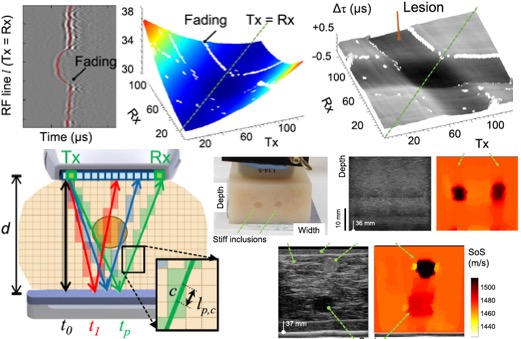

[2022] Bhaskara Rao Chintada, Richard Rau, and Orcun Goksel:

"Spectral Ultrasound Imaging of Speed-of-Sound and Attenuation Using an Acoustic Mirror",

Frontiers in Physics 10(860725), May 2022.

[2022] Bhaskara Rao Chintada, Richard Rau, and Orcun Goksel:

"Spectral Ultrasound Imaging of Speed-of-Sound and Attenuation Using an Acoustic Mirror",

Frontiers in Physics 10(860725), May 2022.

@article{Chintada_spectral_22,

author = {Bhaskara Rao Chintada and Richard Rau and Orcun Goksel},

title = {Spectral Ultrasound Imaging of Speed-of-Sound and Attenuation Using an Acoustic Mirror},

journal = {Frontiers in Physics},

year = {2022},

volume = {10},

number = {860725},

url = {https://arxiv.org/abs/2201.01435},

doi = {10.3389/fphy.2022.860725}

}

[2021] Richard Rau, Ozan Unal, Dieter Schweizer, Valery Vishnevskiy, and Orcun Goksel:

"Frequency-Dependent Attenuation Reconstruction with an Acoustic Reflector",

Medical Image Analysis 67(101875):1-9, Jan 2021.

[2021] Richard Rau, Ozan Unal, Dieter Schweizer, Valery Vishnevskiy, and Orcun Goksel:

"Frequency-Dependent Attenuation Reconstruction with an Acoustic Reflector",

Medical Image Analysis 67(101875):1-9, Jan 2021.

* Runner-up for the MICCAI Elsevier MedIA Prize

@article{Rau_frequency-dependent_21,

author = {Richard Rau and Ozan Unal and Dieter Schweizer and Valery Vishnevskiy and Orcun Goksel},

title = {Frequency-Dependent Attenuation Reconstruction with an Acoustic Reflector},

journal = {Medical Image Analysis},

year = {2021},

volume = {67},

number = {101875},

pages = {1-9},

url = {https://arxiv.org/abs/2003.05658},

doi = {10.1016/j.media.2020.101875}

}